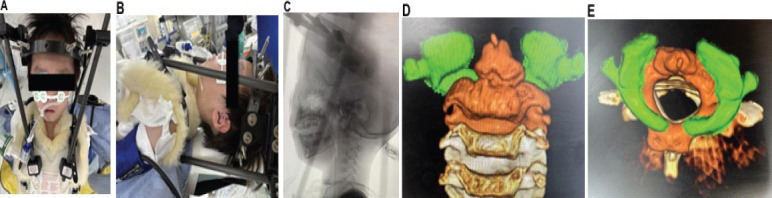

Case report: A 5-year-old boy presented with a history of 22q.11.2 deletion syndrome, DiGeorge syndrome, congenital left-sided clubfoot, and periodic vomiting. He was referred to a local pediatrician with neck pain and torticollis and was prescribed analgesics. After 5 days of no improvement, he was referred to a local pediatric orthopedic hospital where he was diagnosed with AARF (Fielding classification type III). The patient was then referred to our department for traction and orthotic therapy. Computed tomography revealed no deformity of the atlanto-axial articular surface and no evidence of bony fusion between the left and right posterior arches of the atlas. Following conservative treatment, the patient's neck pain and torticollis improved, and imaging confirmed the deformity had corrected. He was discharged on day 32. The symptoms recurred on day 42, and although traction and orthotic therapies were repeated, no improvement was observed. A halo vest was applied on day 59 after symptom onset. As the deformity was corrected, the halo vest was removed on day 94 and the patient continued to wear an orthosis. The patient recurrenced on day 104 and internal fixation was performed on day 120. Two 2.4-mm hollow screws were inserted using the Magerl method. No recurrence was observed at 213 days after onset, and bone union was confirmed by imaging test, and the brace was removed.